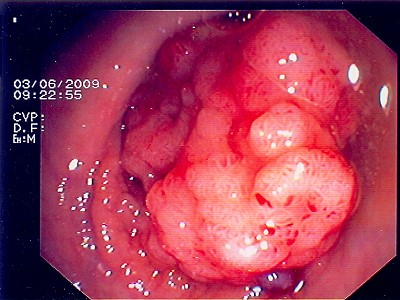

Wie bei den Abbildungen 28 und 30 handelt es sich um einen breitbasigen, relativ flachen, noch nicht entarteten Polyp, der sich mit einer Schlinge nicht vollständig abtragen ließe.